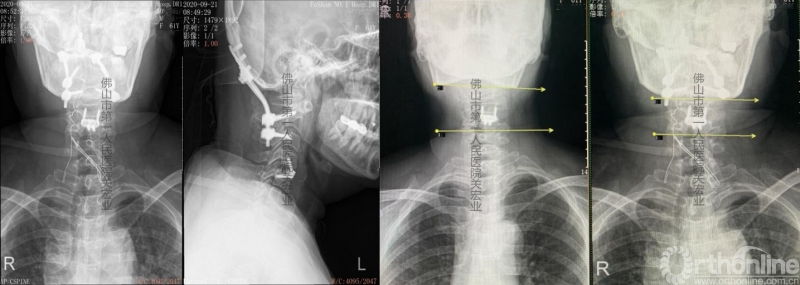

术后分析:

影像学术前、术后对比

A:术后颈后、枕部向头顶的放射痛明显缓解。左上肢肌力提高一级,双侧下肢本体感觉改善。术前寰枢椎旋转脱位、下颌偏歪、齿状突上移、脊髓向右侧偏移的情况,术后影像学可见均有明显改善。